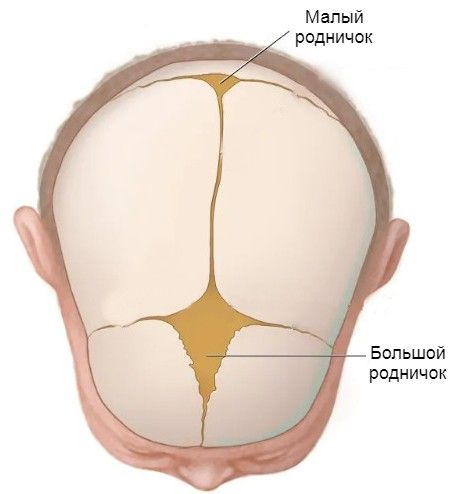

- малый родничок открыт, большой родничок увеличен;

Роднички в норме

- кости черепа мягкие;

- не закрыты швы черепа;